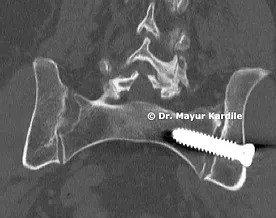

Atlanto Axial Instability

61 yr gentleman